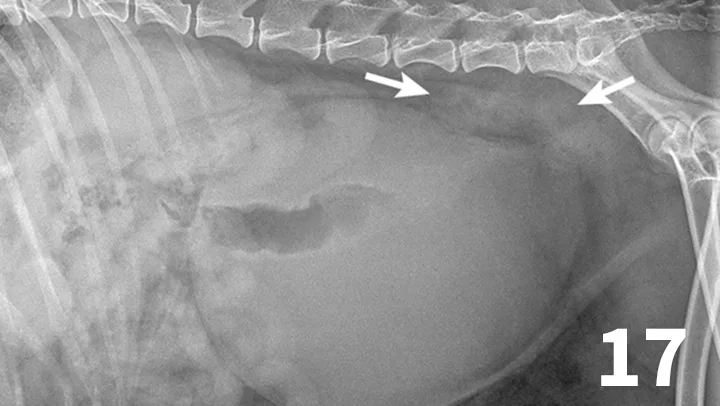

Survey radiographs of the urinary bladder are helpful for evaluation of size and location and for detection of radiopaque calculi. Urinary bladder distention is readily detected (Figure 17). Radiographs are of limited value in evaluating mural disease because the bladder wall cannot be differentiated from the fluid contained within the bladder. Bladder wall thickening (eg, bacterial inflammation, polypoid cystitis, neoplasia) is best evaluated by ultrasonography or double-contrast cystography (Figure 18). It should be noted that the degree of bladder filling can affect bladder wall thickness. For example, a small, mildly distended bladder may appear to have a thickened bladder wall on ultrasound compared with a moderately or severely distended bladder (Figure 19). This potential disadvantage can often be overcome by reevaluating the bladder several hours after preventing voiding.

Figure 17.

This dog had a severely distended urinary bladder on evaluation of lateral abdominal radiographs. Ill-defined, soft tissue opacity was present in the region of the medial iliac lymph nodes (arrows). The dog had urethral neoplasia, which was the cause of the urinary outflow obstruction and lymph node enlargement.